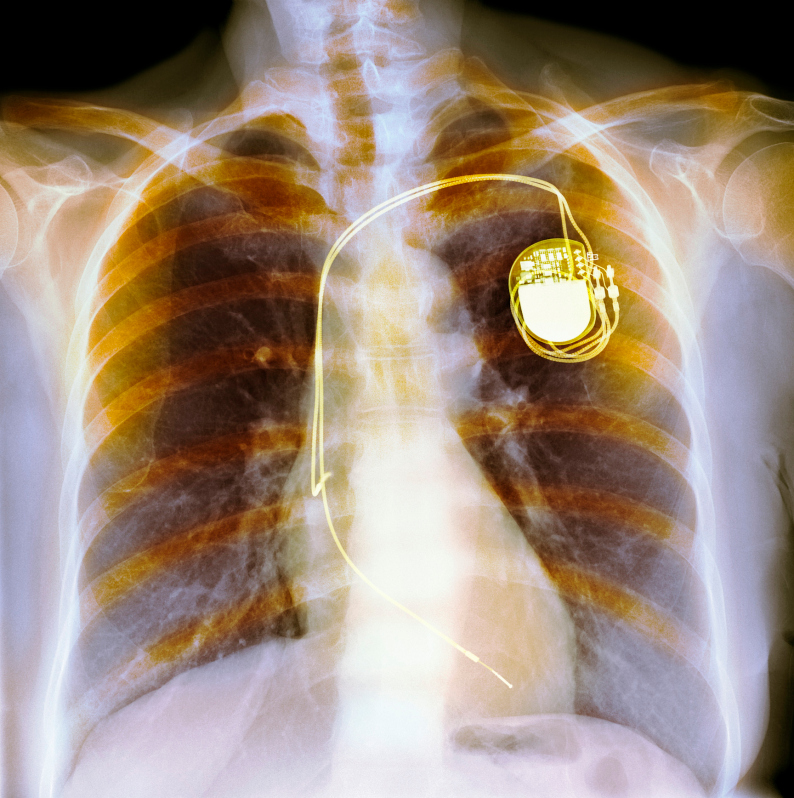

Implantable Defibrillator (Pacemaker) Stock Image C004/7525 Pacemaker And Defibrillator Combined Surgery most pacemakers and icds (implantable cardioverter defibrillators) are implanted in the upper left side of the chest. an icd isn't the same as a pacemaker. Karen hogg, consultant cardiologist at. pacemakers and implantable cardioverter defibrillators (icds) are different types of implanted electronic devices that treat slow, abnormal and. How does a pacemaker work? Defibrillators deliver a shock. Pacemaker And Defibrillator Combined Surgery.

Implantable Defibrillator (Pacemaker) Stock Image C004/7524 Pacemaker And Defibrillator Combined Surgery How does a pacemaker work? Defibrillators and pacemakers help the heart maintain a regular rhythm. most pacemakers and icds (implantable cardioverter defibrillators) are implanted in the upper left side of the chest. Karen hogg, consultant cardiologist at. pacemakers and implantable cardioverter defibrillators (icds) are different types of implanted electronic devices that treat slow, abnormal and. an icd. Pacemaker And Defibrillator Combined Surgery.